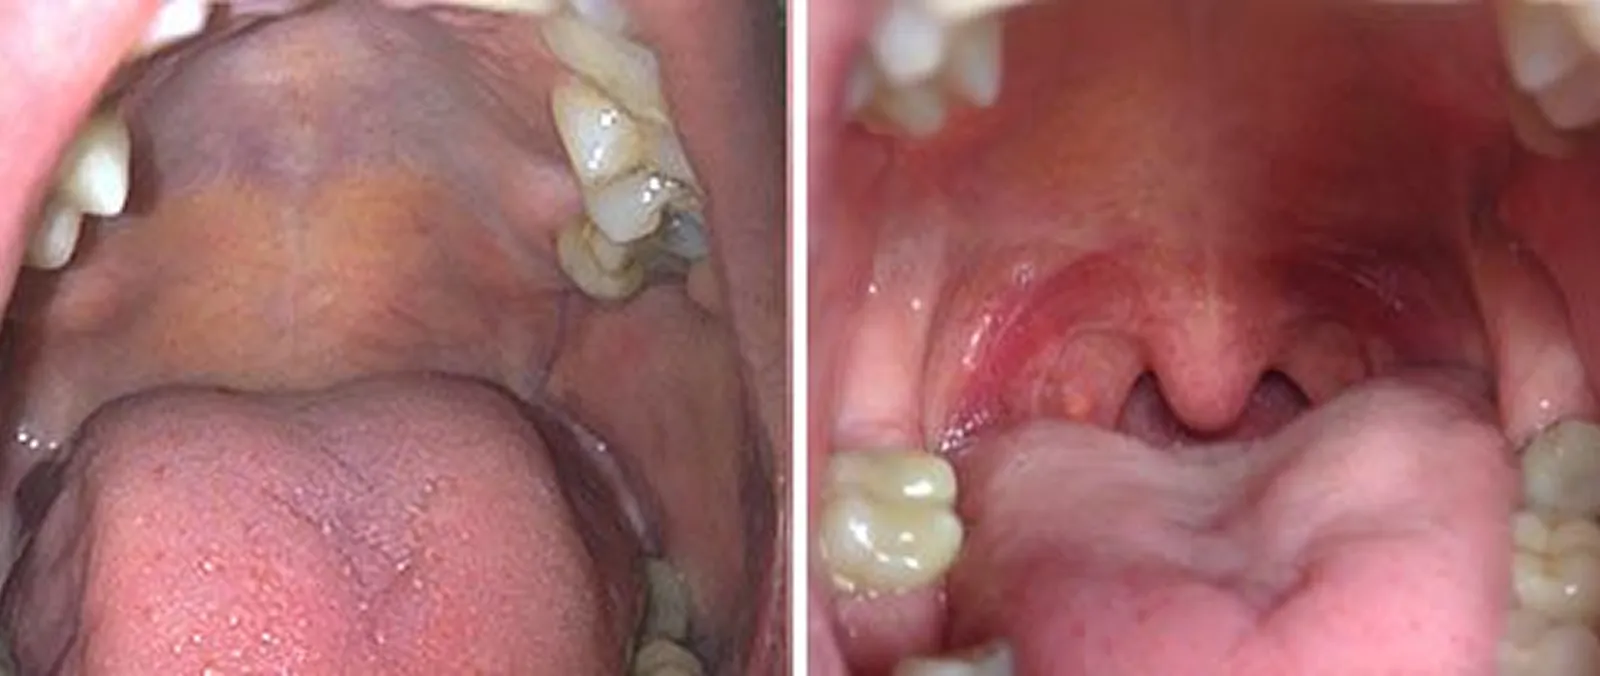

Le traitement au laser agit directement sur les tissus situés à l’arrière de la gorge, souvent responsables du ronflement lorsqu’ils se relâchent et vibrent pendant le sommeil.

En chauffant doucement ces tissus, le laser stimule la production de collagène et améliore leur tonicité, ce qui permet de réduire les vibrations et de favoriser une respiration plus fluide durant la nuit.

• 2 Application du laser à l’arrière de la bouche

• 3 Traitement des zones ciblées (muqueuses)